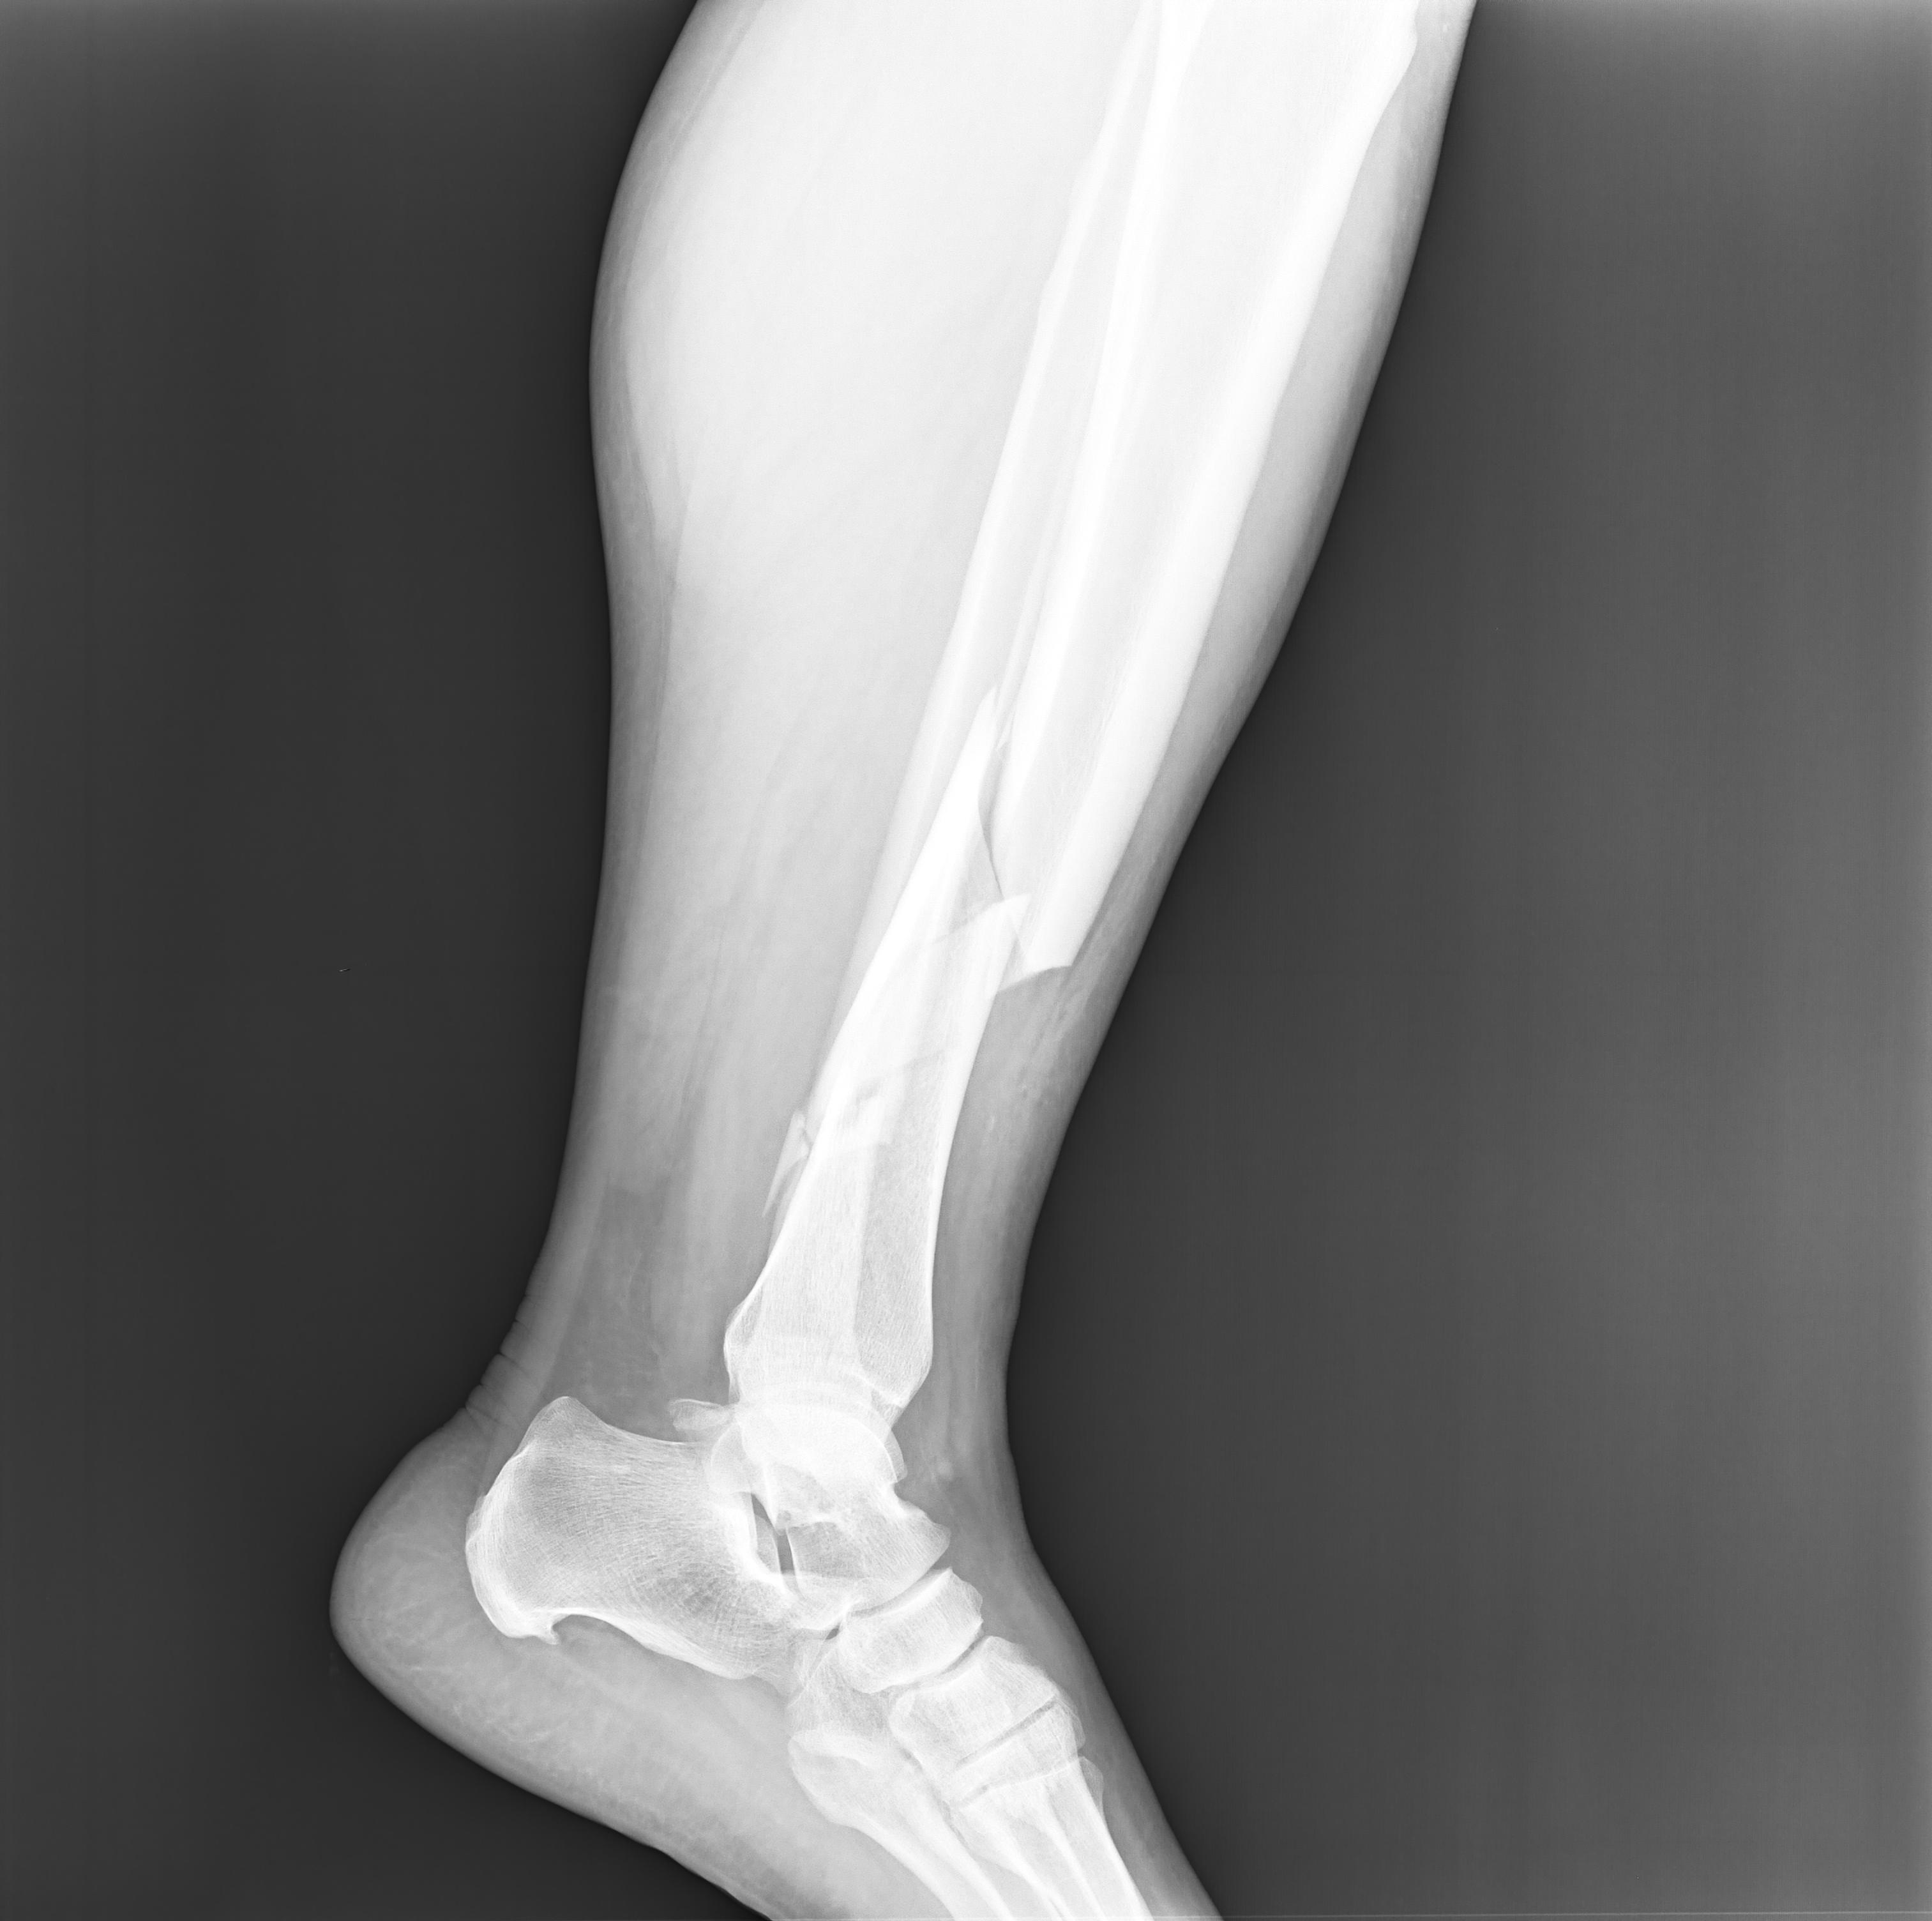

Read More[caption id="attachment_2601" align="alignnone" width="2476"] ameliyat öncesi[/caption] [caption id="attachment_2602" align="alignnone" width="1047"] kapalı yöntemle vidalama[/caption]...